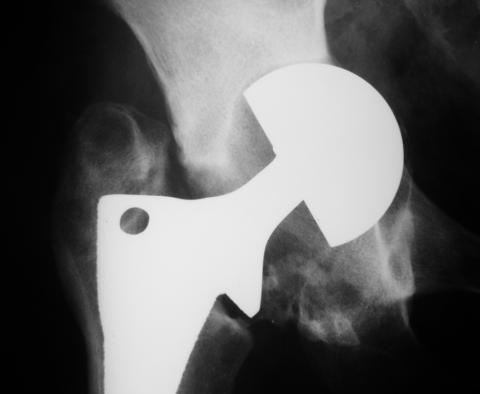

Лечился в стержневом аппарате по месту жительства. АВФ демонтировали через полгода из-за воспаления в области стержней (рис 2). После демонтажа в течение месяца больной лихорадил до 38*, были боли в бедре. Эти явления исчезли после курса антибиотиков. Через год после травмы в ЦРБ ему имплантировали биполярный протез (рис 3). Рана зажила первично. Ходил с костылями, слегка приступая на ногу. На контрольных осмотрах выявлена прогрессирующая протрузия (рис 4-6).

Планируем через малый разрез взять образцы тканей для тщательного бакисследования. При отсутствии инфекции - поставим антипротрузионное кольцо Мюллера с цементной чашкой и костной пластикой из гребня подвздошной кости. В противном случае - выкинем все железо.

Если нет явных признаков воспаления (клинических и лабораторных) то я бы предпринял одноэтапную ревизию с заменой обоих компонентов сутава. Кольцо

Мюллера не есть антипротрузионное - это моделирующее кольцо и вряд ли здесь подойдет. В данном случае - кольцо Бурша -Шнайдера или Ганса более логичны, так как они истино антипротрузионные. Огромный дефект следует закрыть костью на будущие ревизии. При инфекции - шанс на двухэтапную ревизию есть, но риски значительные. риски выбирает пациент. В любом случае - это следует делать умелыми руками при хорошем материальном обеспечении. А Рыков.